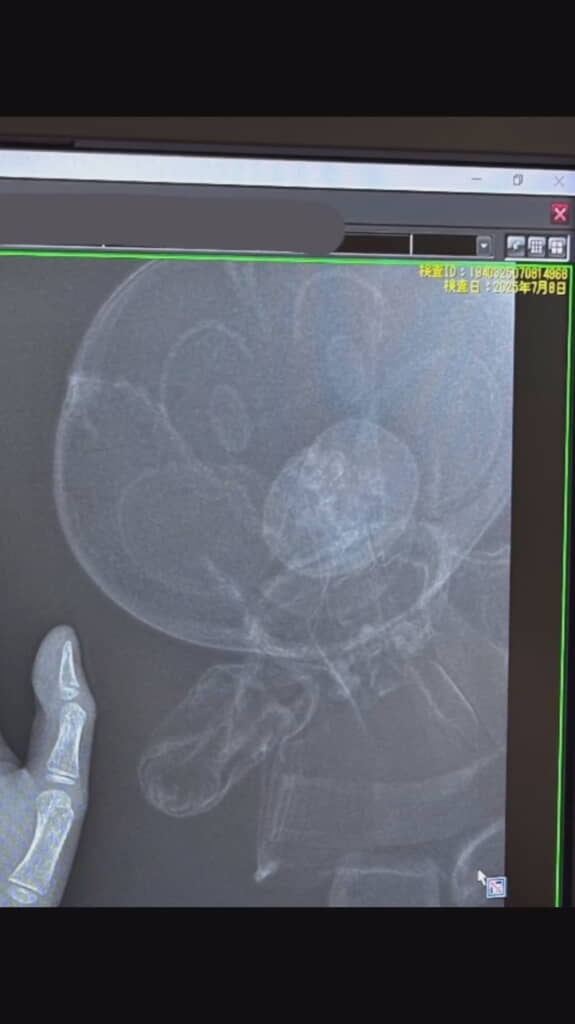

整形外科で手のレントゲン検査をし、経過を観測していたところ、思わぬものが映っていました。診察中、「整形外科の先生めっちゃ笑ろてはるなぁ」と見守っていたIKUEさんがよくよく見たところ、レントゲン写真に映る手の右側にアンパンマンがいたのです!

横向きの写真では手と横顔のアンパンマンが向き合っているように、そして正面からはツーショット状態です。お兄ちゃんの手と一緒に顔だちもくっきり映し出されているアンパンマン。これは確かに思わず笑ってしまいますね。

レントゲン室にはいろんなぬいぐるみが置いてあり、一緒に撮影してもOKだったとのこと。今回のユニークな写真は、息子さんの「一緒に取りたい」という希望もあって出来上がったもののようです。お兄ちゃんはあとから「ミッキーとも撮りたかった」と言っており、そんな息子さんに「ディズニーちゃうねん」とツッコミをいれるIKUEさんでした。